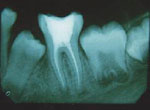

Root Canal Therapy